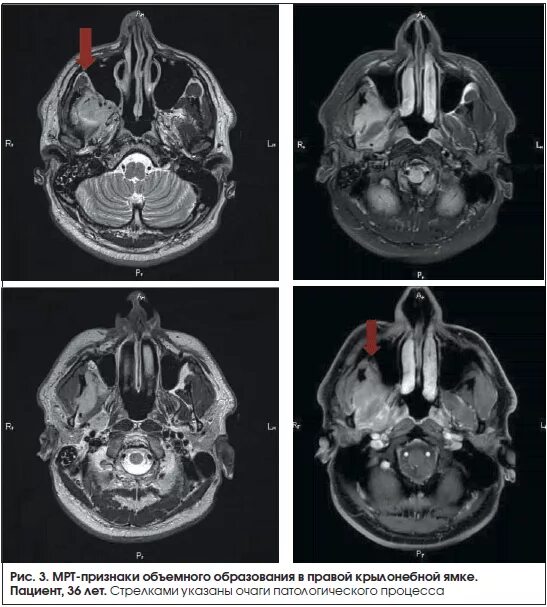

Мрт симптомы